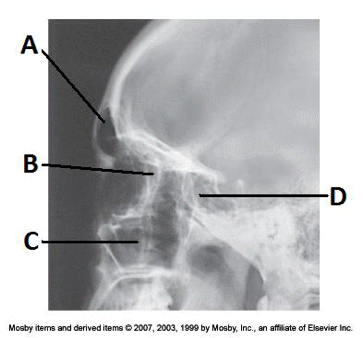

4. Examine the image of the paranasal sinuses below. The letter D labels the:

a. maxillary sinuses

b. ethmoid sinuses

c. sphenoid sinuses

d. frontal sinuses

____ 136. Examine the image of the paranasal sinuses below. The letter B labels the:

a. frontal sinuses

b. maxillary sinuses

c. ethmoid sinuses

d. sphenoid sinuses

cc. ethmoid sinuses

____ 184. Examine the image of the paranasal sinuses below. The letter B labels the:

b. sphenoid sinuses

c. frontal sinuses

d. ethmoid sinuses

aa. maxillary sinuses

____ 191. Examine the image of the paranasal sinuses below. The letter C labels the:

a. ethmoid sinuses

c. petrous ridge

bb. maxillary sinuses